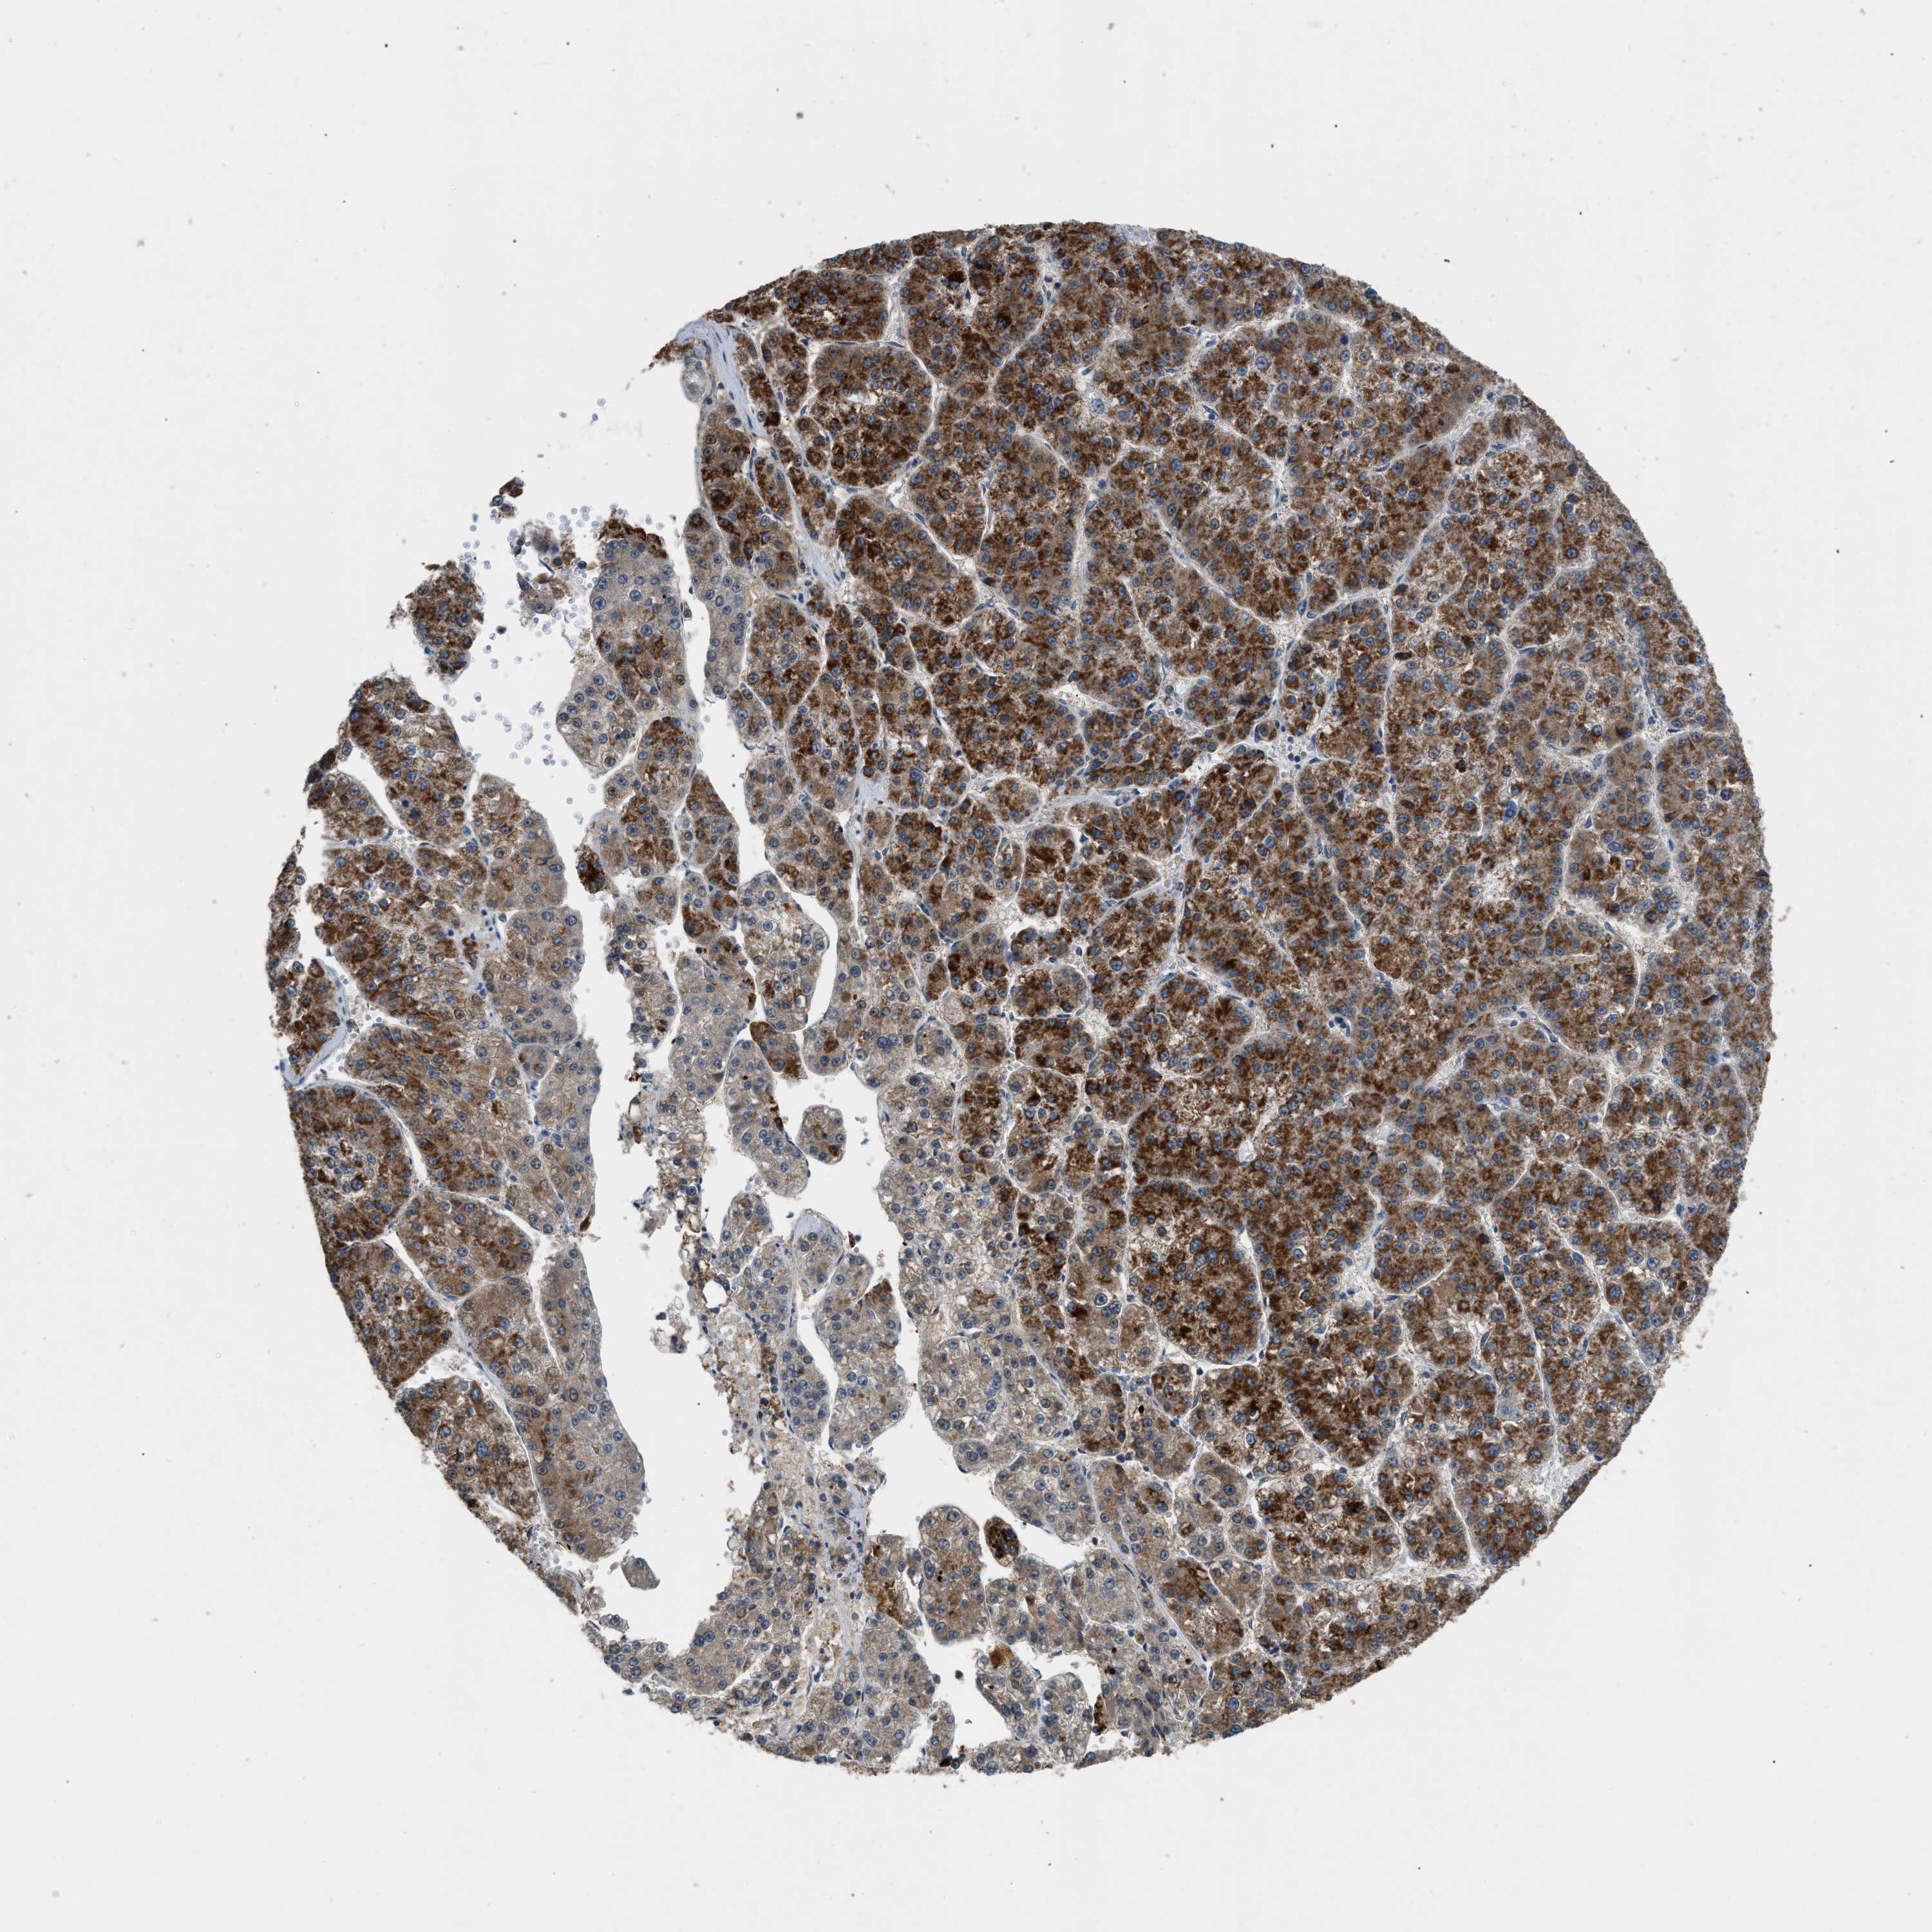

LIVER CANCER - Protein expressioni

A mouse-over function shows sample information and annotation data. Click on an image to view it in a full screen mode. Samples can be filtered based on level of antibody staining by selecting one or several of the following categories: high, medium, low and not detected. The assay and annotation is described here.

Note that samples used for immunohistochemistry by the Human Protein Atlas do not correspond to samples in the TCGA dataset.

Antibody stainingi

Antibody staining in the annotated cell types in the current human tissue is reported as not detected, low, medium, or high, based on conventional immunohistochemistry profiling in selected tissues. This score is based on the combination of the staining intensity and fraction of stained cells.

Each image is clickable and will lead to virtual microscopy that enables deeper exploration of all samples and also displays staining intensity scores, fraction scores and subcellular localization as well as patient and tissue information for each sample.

Antibody HPA018910

Antibody HPA018921

Antibody HPA018923

Staining

High

Medium

Low

Not detected

Intensity

Strong

Moderate

Weak

Negative

Quantity

>75%

75%-25%

<25%

None

Location

Nuclear

Cytoplasmic/membranous

Cytoplasmic/membranous,nuclear

Cholangiocarcinoma

Carcinoma, Hepatocellular, NOS